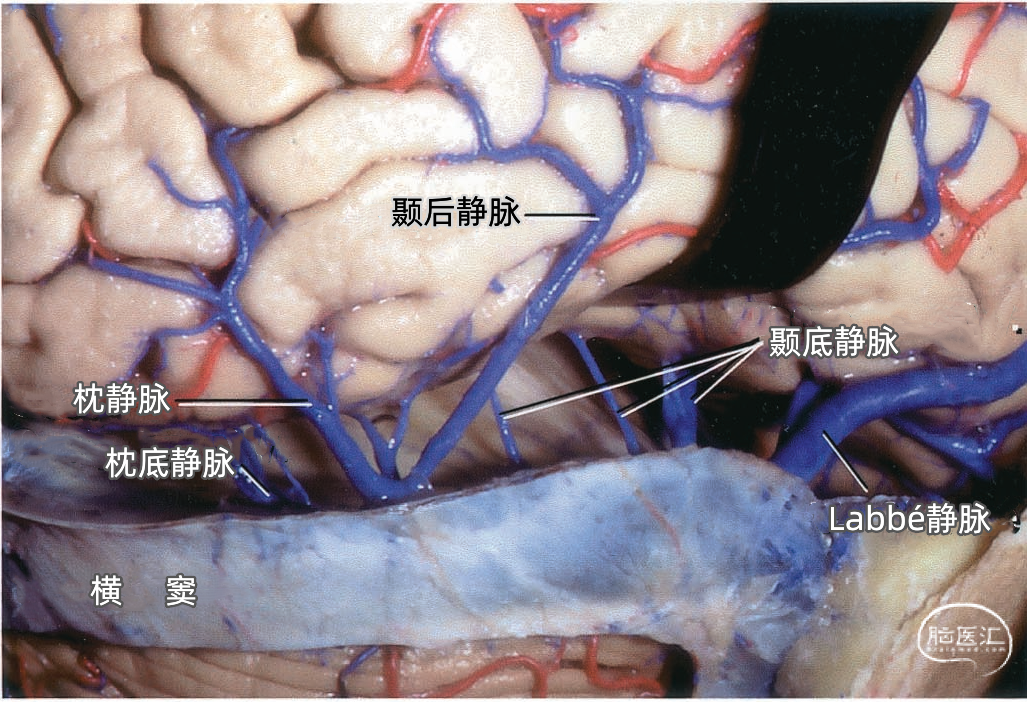

颞叶外侧面的皮层静脉可引流入横窦(上图),但在流入横窦之前,它们常向内沿颞叶底面进入小脑幕的短窦,此窦进入横窦末端之前在小脑幕内走行大约1cm。来自颞叶和枕叶底面的皮层静脉通常汇入外侧小脑幕窦。 Labbé静脉通常终于横窦(上图),但也可弧形围绕大脑半球下缘汇入外侧小脑幕窦。▼9.小脑幕窦

下图示汇入外侧小脑幕窦的颞底静脉、枕底静脉。左侧红色箭头指示左侧汇入小脑幕窦属支的颞底长静脉。颞底静脉汇入有多个属支的小脑幕窦。右侧黄色箭头显示汇入右侧小脑幕窦的静脉属支。 下图示(左侧)颞底静脉和枕底静脉汇聚于两个横窦内侧的短小脑幕窦。(右侧)Labbé静脉和颞后静脉直接引流入横窦。左侧小脑幕的另一个窦(小脑幕内侧窦)(黄色箭头)接受来自小脑的引流,向内侧经过小脑幕汇入窦汇。

下图示右侧枕底静脉,颞底静脉。从后颞下入路抬起颞底到达小脑幕游离缘时,除了可能牺牲Labbé静脉和来自颞叶、枕叶外侧面的静脉外,还可能需要牺牲多条汇入小脑幕窦的颞底静脉和枕底静脉。

Labbé静脉也称下吻合静脉,是跨越颞叶外侧,连接外侧裂与横窦之间的最大吻合静脉。它通常起自外侧裂中部,行向后下,进入横窦前部。 Labbé静脉经过颞叶表面的位置有可能非常靠后甚至位于颞叶的最后界,或非常靠前达颞叶前1/3的外侧面。在此研究的20例半球中,12例Labbé静脉位于颞中静脉水平,6例位于颞后静脉水平,2例位于颞前静脉水平。有时会有两条Labbé静脉,其中后支通常会粗大一些。

下图示横窦和小脑幕窦的分支。抬起颞叶的后部,暴露进入横窦的Labbé静脉、颞后静脉和枕后静脉,从颞叶底面进入小脑幕窦的颞底静脉。

一些颞叶和枕叶凸面外侧的静脉并不直接注入横窦,而是转向内侧达颞叶底面汇入小脑幕窦。

下图示放大观。从前方暴露Labbé静脉。从后部颞下入路手术,可能牺牲Labbé静脉和来自颞叶、枕叶外侧面的静脉,还可能需要牺牲多条汇入小脑幕窦的颞底静脉和枕底静脉。

下图示小脑幕的上面观。右侧Labbé静脉和颞后静脉直接引流入横窦。